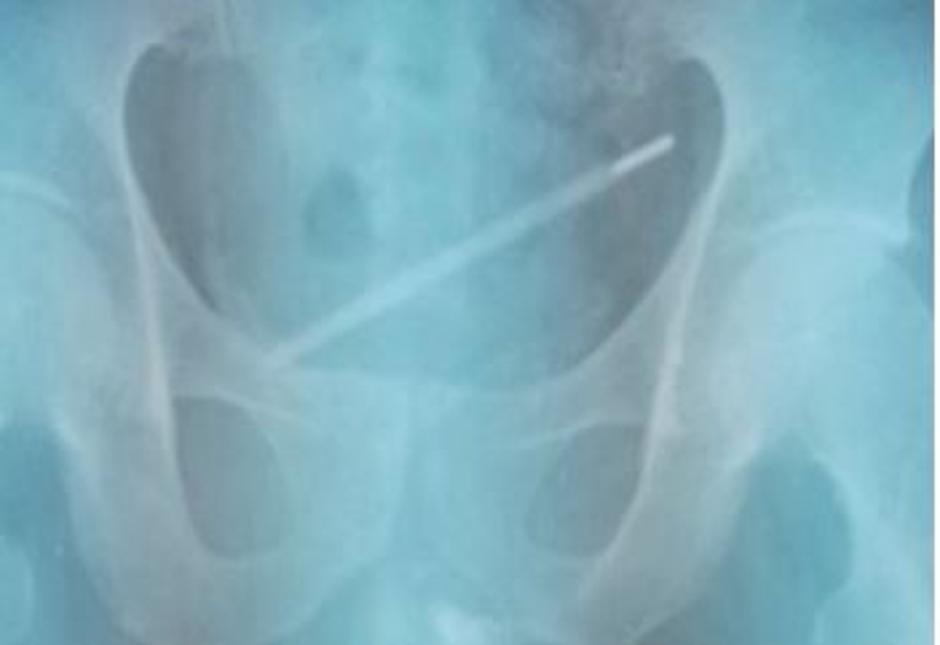

Neimenovani moški iz Šanghaja je poiskal pomoč na urgenci po tem, ko je v urinu opazil kri. 25-letnik je pozneje priznal, da si je 11 dni pred tem v penis vtaknil stekleni termometer.

Čeprav je povedal, da mu je ob tem bilo prijetno, mu je bilo pozneje zagotovo žal. Čakala ga je namreč nadležna preiskava, da bi odkrili, kjer se tujek nahaja. Bolniku so opravili cistokopijo, kar pomeni, da so mu v sečnico vstavili cev s pritrjeno kamero. Ugotovili so, da je termometer že "prilezel" v mehur.

Urologi so termometer nato izvlekli, kar je trajalo 15 minut in bolnika naslednji dan že spustili iz bolnišnice, navaja Urology Case Reports, kjer urologi iz celega sveta poročajo o nenavadnih primerih - o bizarnih početjih ljudi, ki si s takšnimi ali drugačnimi spolnimi praksami ogrožajo življenje.